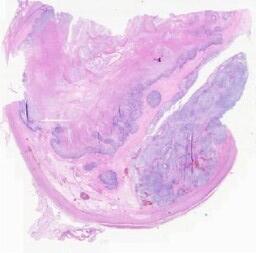

临床资料: 患者,女,60岁。因“腹胀1周,检查发现盆腔包块半天”入院。妇科检查:子宫附件分辨不清,盆腔扪及约10cm包块,稍偏右侧,质硬,边界清,不活动,无压痛。彩超检查:腹盆腔探及液性暗区,盆腔探及范围约9.9×6.9cm的混合回声团,形态规则,边界清楚(增大子宫?其它?)。CT检查:盆腔(增强扫描)右侧附件区见团块状囊实性混杂密度影,大小约91×76mm,增强实性成分可见明显强化,子宫及膀胱未见明显异常,盆腔未见肿大淋巴结,盆腹腔大量积液。糖类抗原测定(CA-125)(血清):541.66μ/ml↑。

大体所见: 送检“右附件及肿瘤”:灰白灰褐色破碎不整形组织一堆,总体积10cm×9cm×6cm,其中可见卵巢增大,呈囊实性,多方,囊内见水样及胶冻样物质,囊壁见大量菜花样新生物,质脆